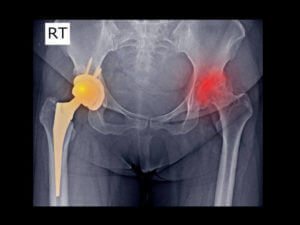

Film X ray DDH and total hip replacement

Total hip replacement, or total hip arthroplasty, is commonly prescribed for chronic and debilitating hip pain due to damage to the cartilage and bone. In this procedure, the damaged components are removed and replaced with artificial prosthetics during the surgery. Once your provider clears you for total hip arthroplasty, the next step is preparing. Proper